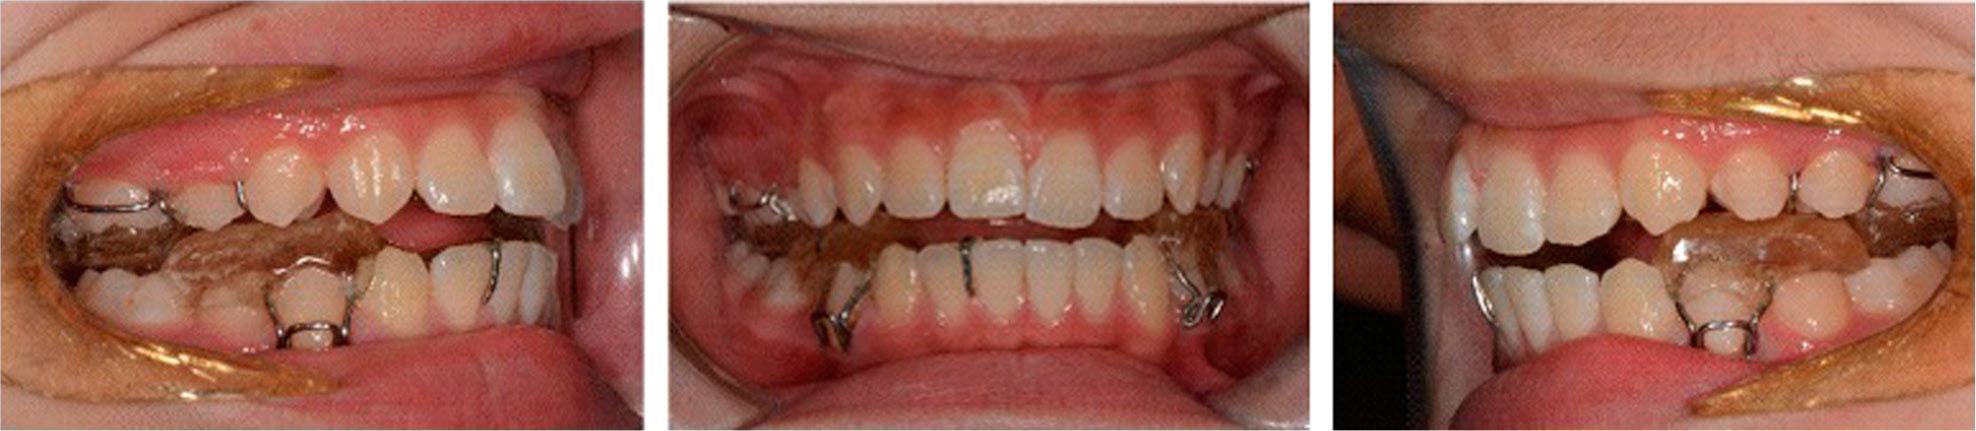

Figure 5.

Figure 6.